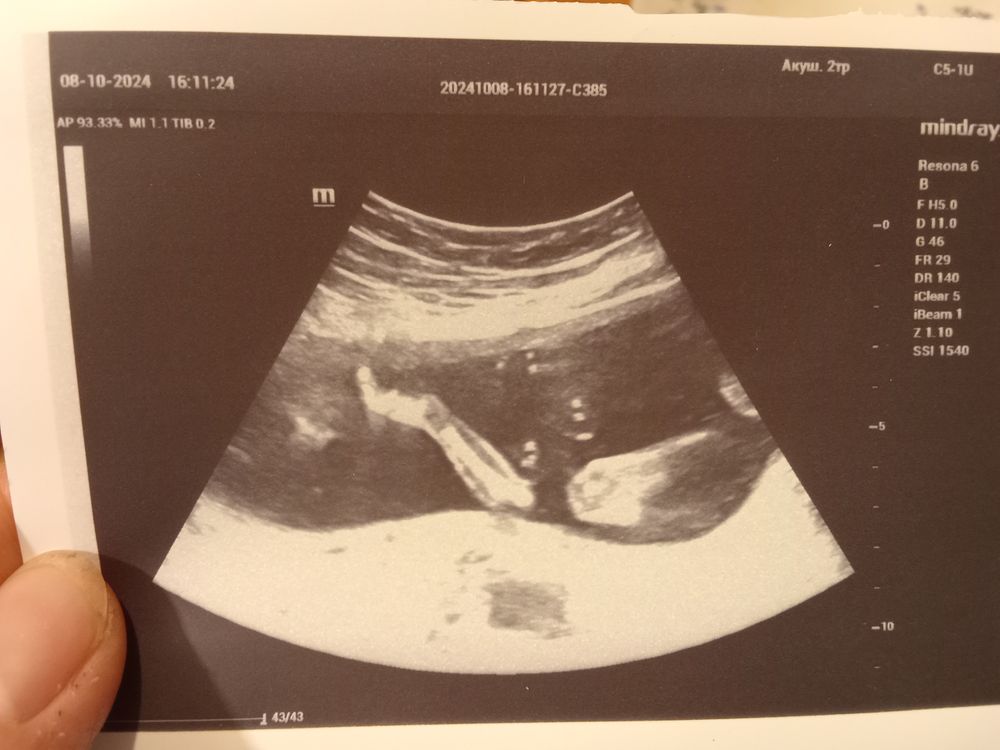

2 скрининг

Поздравляю Катюш🌸❤️ у меня тоже сидит в тазовом, но время вроде есть ещё что бы им спокойно перевернутся, на счет шейки пока нормально но лучше контролировать, у меня на 2 скрининге 28мм намерили, отправили в больницу.

Яна, спасибо ❤️ ну да, насчёт тазового пока не переживаю, да и в любом случае уже не так страшно после первых родов) по шейке узист сказала, что хорошая 32, а если по-другому как-то мерить, вообще 41. Ну в любом случае спрошу у врача на следующей неделе. А что в больнице тебе будут делать? Наблюдать пока или пессарий?

Поздравляю! У меня все узи дамочка была на попе, в 29 смотрели и где плацента, и длину свободного конца пуповины и что там только не вы смотрели - все ок, а она на попе. В 33 перевернулась